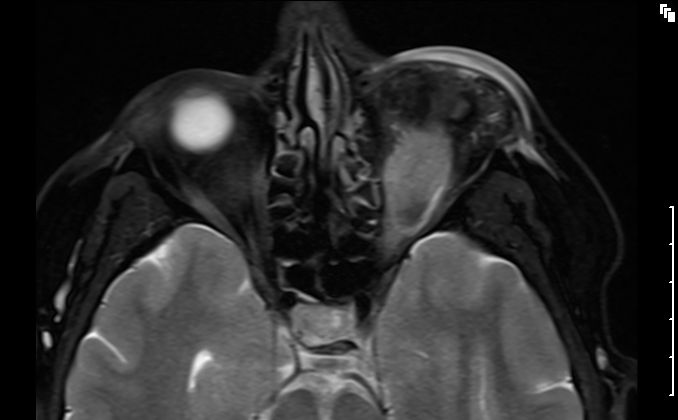

MRT eines retroorbitalen Lymphoms |